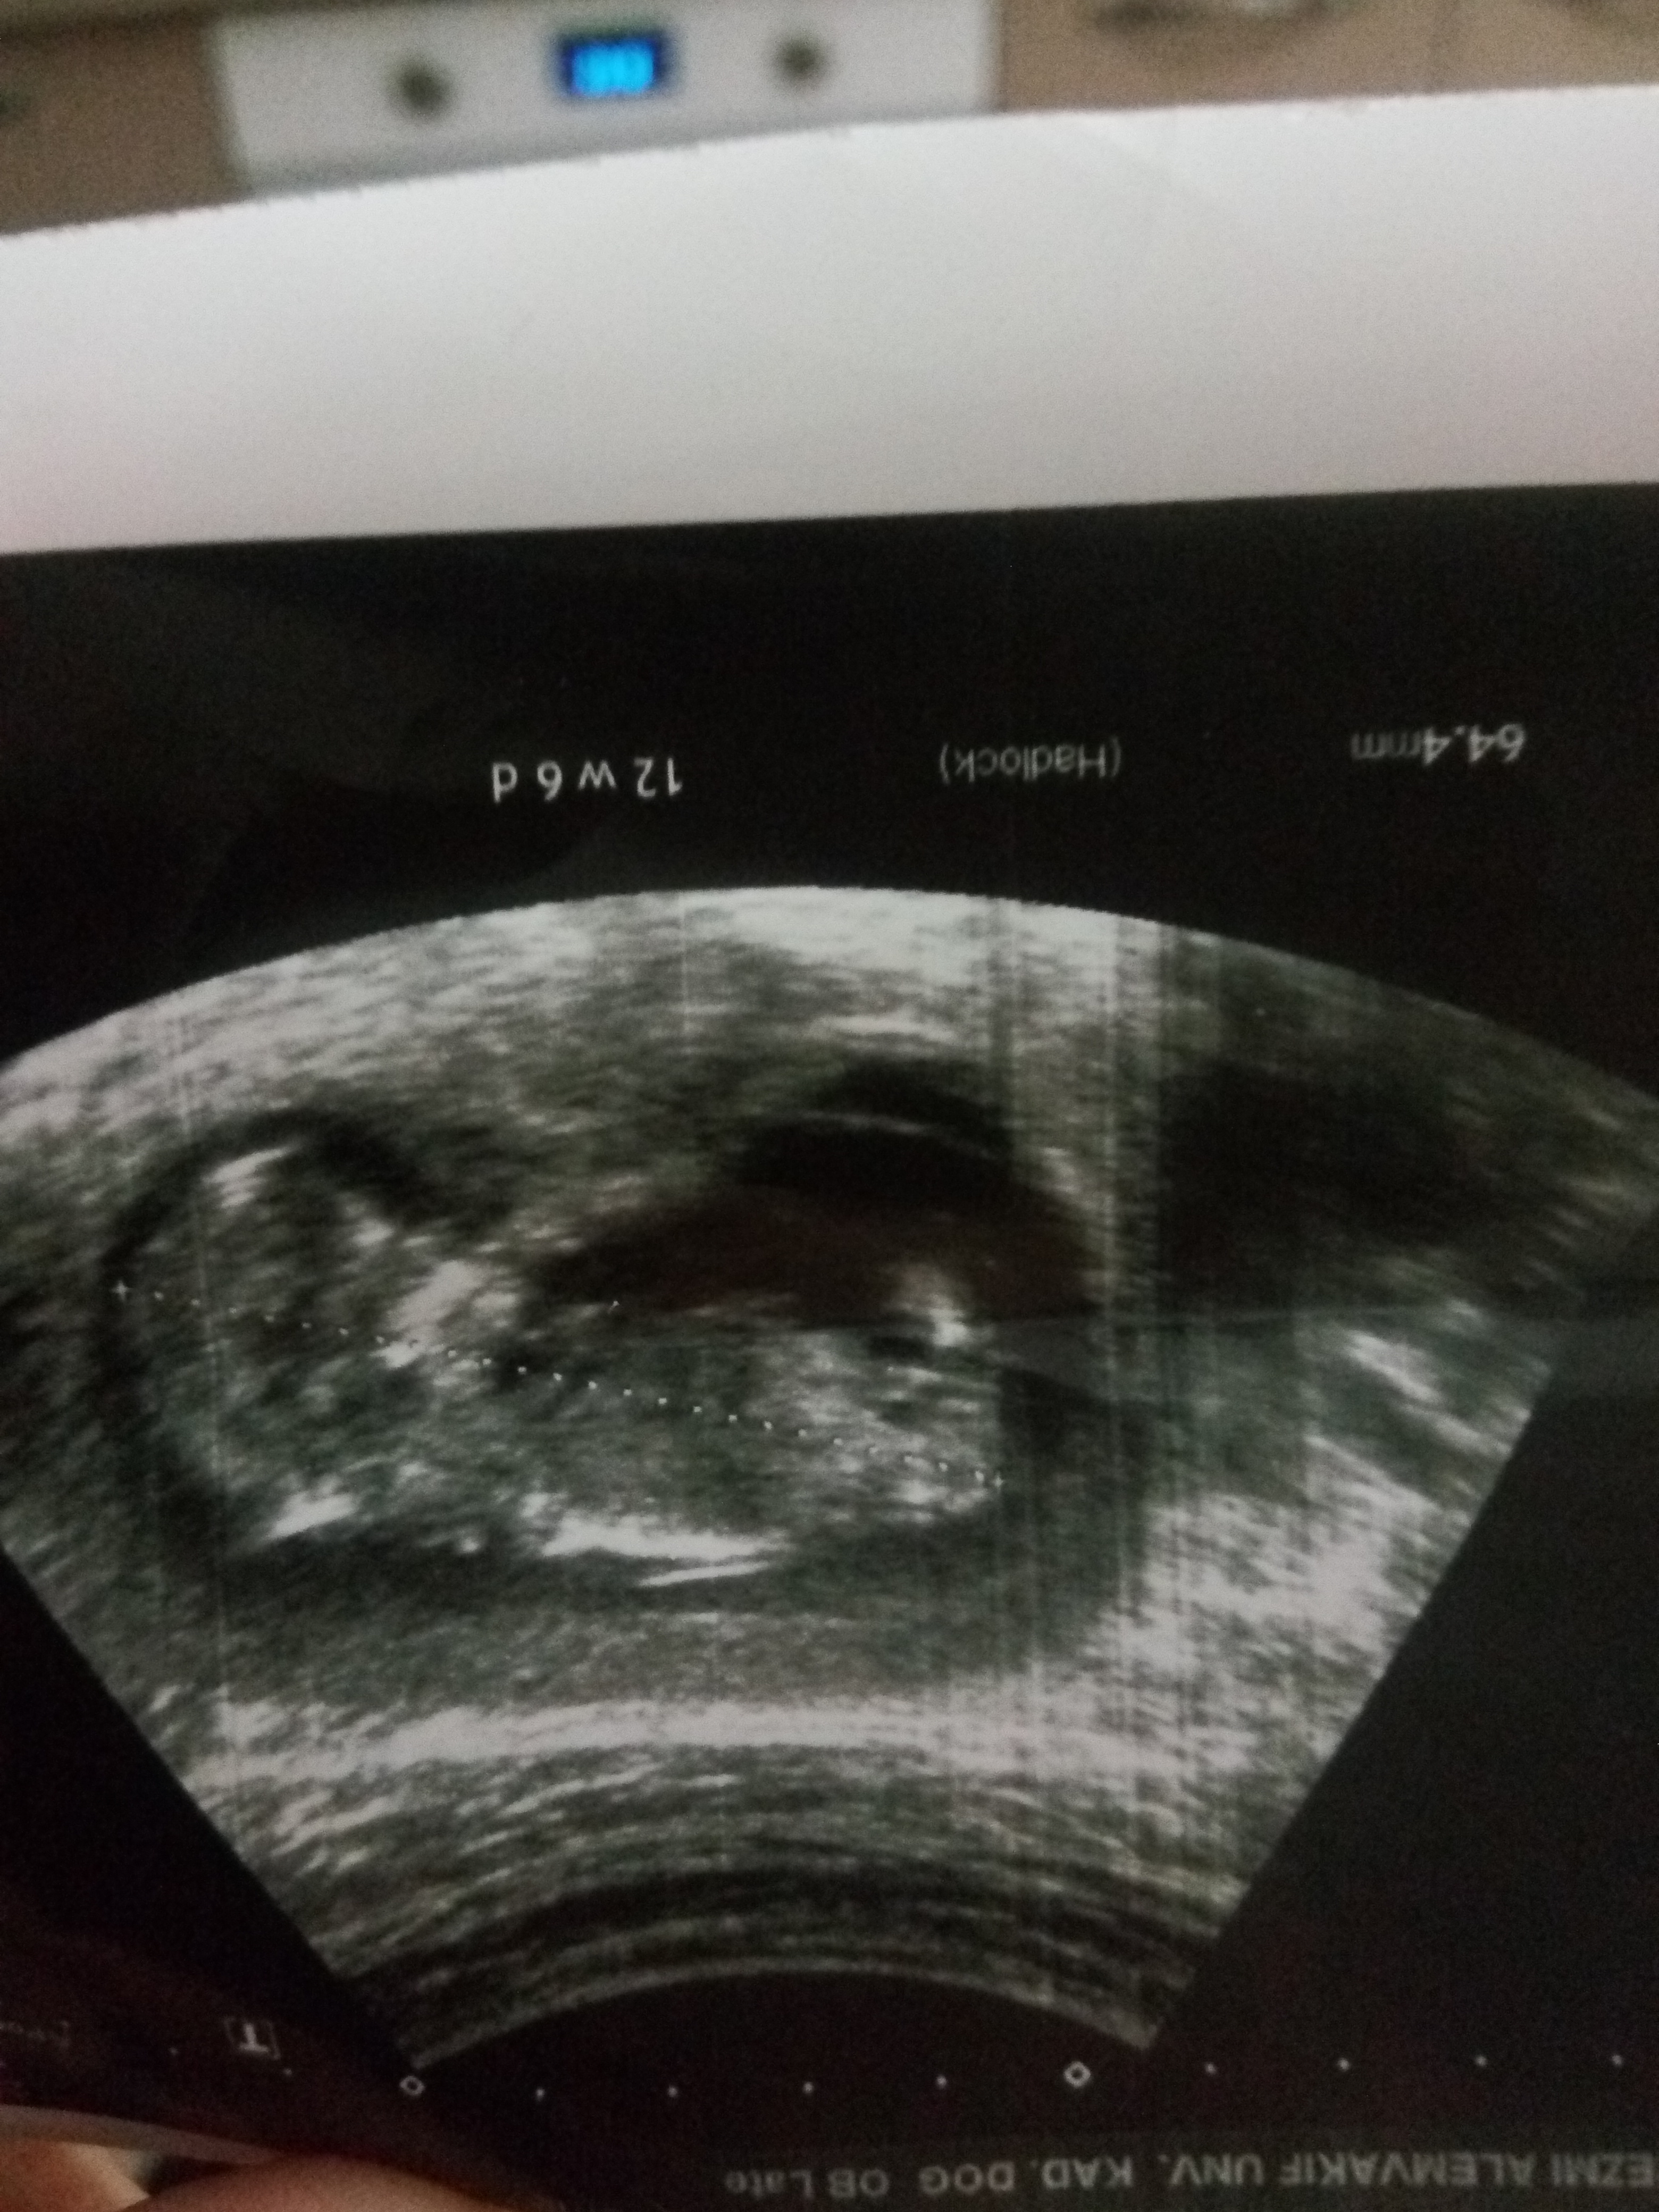

Merhabalar aranıza yeni katıldım ben. İlk konumuda açtım acaba aranızda bebeğimin cinsiyeti için bana yardımcı olacak kimse var mı ? Arkadaslar kiz mi erkk mi bi bakar misiniz

Merhaba emin olmamakla birlikte bebeğinizin cinsiyeti erkeğe benziyor . Bebeğin cinsiyeti 16-17 haftalarda daha net izlenir. 20. haftaya yaklaştıkça cinsiyet en net şekilde değerlendirilir. Nadiren cinsiyet tespitinde yanılmalar olabilir.Sağlıklı gebelik geçirmeniz dileği ile.